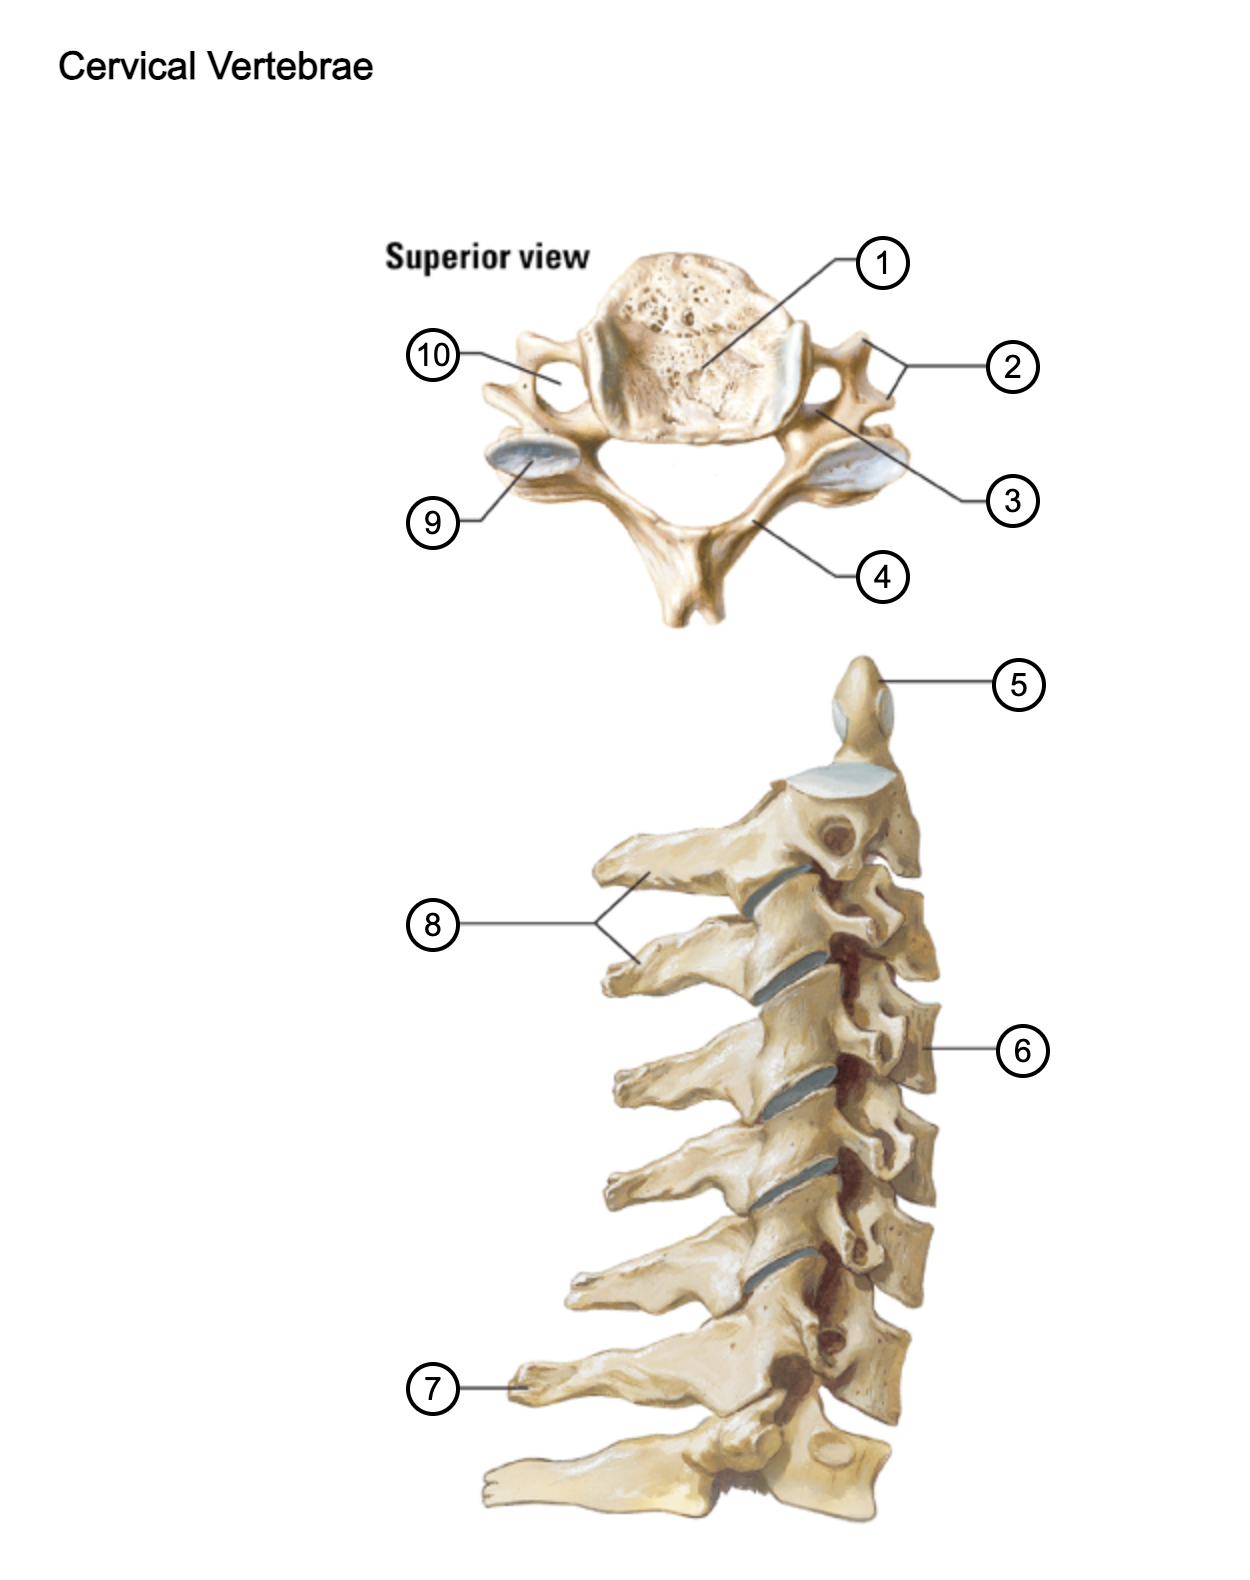

1

vertebral body

2

transverse process

3

pedicle

4

lamina

5

dens axis

6

vertebral body of C4

7

spinous process C7 (vertebra prominens)

8

spinous processes (C2 and C3)

9

superior articular process of C4

10

transverse foramen